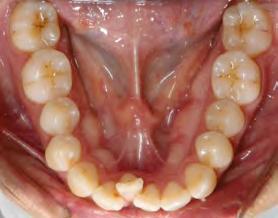

52 | SONRIENDO AL FUTURO

Tratamiento ortodóncico en paciente adulto tratado con extracciones de primeros molares permanentes. Reporte de caso

en paciente adulto tratado con extracciones de primeros molares permanentes. Reporte de caso